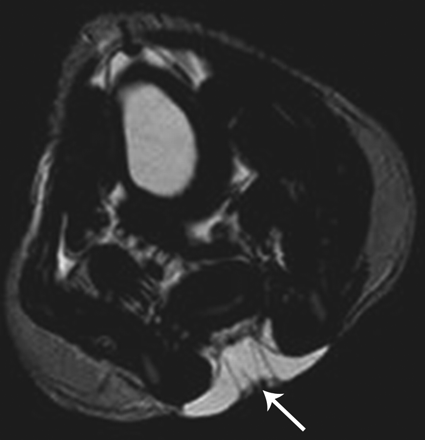

Продолжение.

Приложения:

1.gr_.slayd16.jpg2.pr_.slayd17.jpg3.pr_.slayd18.jpg